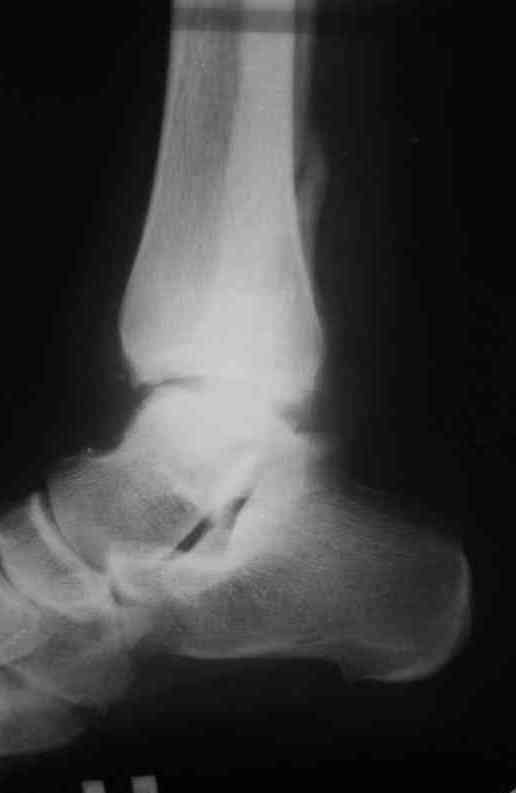

Уважаемые коллеги. Хотелось бы услышать ваше мнение по следующему случаю Обратился больной 23 года, травма 4 месяца назад - закрытый перелом наружной, внутренней лодыжки правой голени. Лечился консервативно, гипсовой иммобилизацией 8 недель, после снятия последней прошел курс восстановительного лечения. Беспокоят боли в области правого голеностопного сустава больше в проекции внутренней лодыжки, к вечеру. Отечность области сустава при физических нагрузках.Походка не изменена. Контуры правого голеностопного сустава сглажены. Имеется вальгусная установка правой пяточной кости. Объем движений в голеностопном суставе подошвенное / тыльное сгибание 50/0/80, безболезненные. Посоветуйте что делать в данной ситуации. Мне видится следующий вариант решения данной деформации: Восстановление нормальной анатомии голеностопного сустава - остеотомия малоберцовой кости и внутренней лодыжки, удалить все рубцы из области дистального межберцового синдесмоза, восстановить длину и устранить ротационное смещения наружной лодыжки.( встанет ли таранная кость на место?), фиксация наружной лодыжки пластиной, внутренней - винтами, дистального межберцового синдесмоза винтом. ЭОПом не располагаем. Что вы посоветуете? Где могут быть - технические трудности, <подводные камни>.

P.S. На боковой проекции таран выглядит несимпатично. Может быть изза качества снимка?